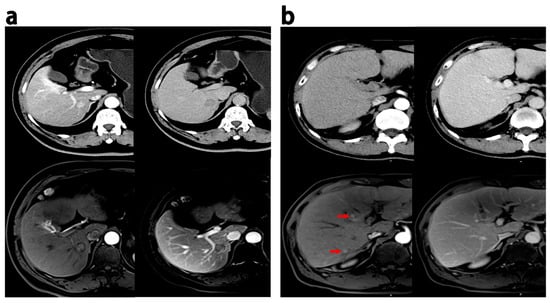

All radiologic traits had an excellent intraobserver and interobserver agreement (kappa > 0.75). Intratumoral necrosis and smooth margins were more frequent on MRI than on CT (p < 0.05). Nine cases showed multilesions, eleven cases displayed pseudocapsules, five cases revealed intratumoral necrosis, six cases demonstrated infiltrative margins, two cases exhibited wash-in, and thirteen cases presented wash-out on MRI but not on CT. Conversely, eleven cases exhibited multiple lesions, twelve had pseudocapsules, eleven had intratumoral necrosis, seventeen had infiltrative margins, five had wash-in, and eight had wash-out on CT scans but not on MRI. Figure 3 provides representative images of discrepant MR imaging and CT findings.

Figure 3.

Discrepant MRI and CT findings in HCCs. (a) HCC patients (recurrence within 18 months after hepatectomy), 60 years, a 1.9 cm HCC; enhancement in the pseudocapsule was observed in the AP, and delayed phase on MRI while the appearance was not observed on CT. (b) HCC patients (ER group), male, 52 years old, 0.6–0.8 cm HCC lesions with wash-in in the AP (red arrow) and partial wash-out in the PVP at MRI; these lesion did not show wash-in and wash-out at CT. PVP = portal venous phase; AP = arterial phase.